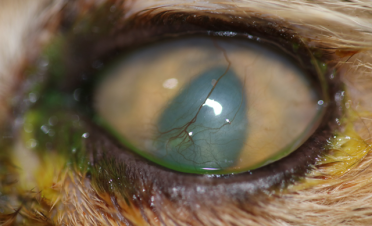

Bagheera es una gatita de raza exotic de 16 años de edad que acudió al IVO porque su ojo izquierdo presentaba una tela blanquecina desde hacía unos 10 días y sus propietarios le notaban el ojo hinchado.

El ojo de Bagheera lagrimeaba mucho, lo mantenía cerrado y tenía mucho dolor.

Durante la exploración oftalmológica, tras instilar una gota de colirio anestésico, pudimos observar una úlcera corneal infectada (úlcera colagenasa o “melting”).

La úlcera abarcaba prácticamente el 90% de la córnea, presentaba una gran inflamación en la conjuntiva y vasos sanguíneos en la periferia de la misma.

Las úlceras colagenasa o “melting” son úlceras altamente infectadas que afectan a capas medias y profundas de la córnea, pudiendo incluso llegar a perforar el ojo. Debido a las enzimas proteolíticas y colagenasas que liberan las bacterias, la córnea pierde su rigidez y adopta una tonalidad azulada y un aspecto gelatinoso, de ahí su apodo “úlcera melting”.